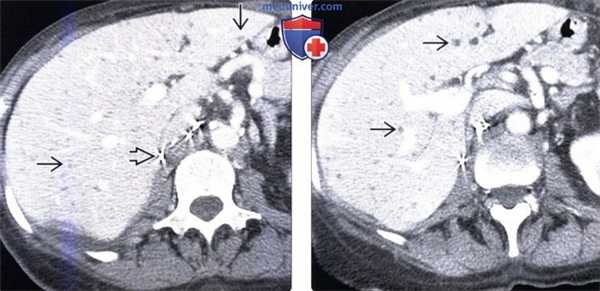

(Слева) На аксиальной КТ с контрастным усилением у женщины 76 лет с верифицированным раком почки визуализируются множественные мелкие гиподенсные очаги, диффузно распределенные в печени. Обратите внимание также на клипсы после нефрэктомии. Билиарные гамартомы в этом случае не следует ошибочно принимать за метастазы.

(Справа) На аксиальной КТ у этой же пациентки определяется большее количество очагов, которые - в чем практически уже нельзя усомниться - представляют собой билиарные гамартомы. Очаги остаются стабильными на протяжении многих лет, при этом иммунный статус пациентки не нарушен.